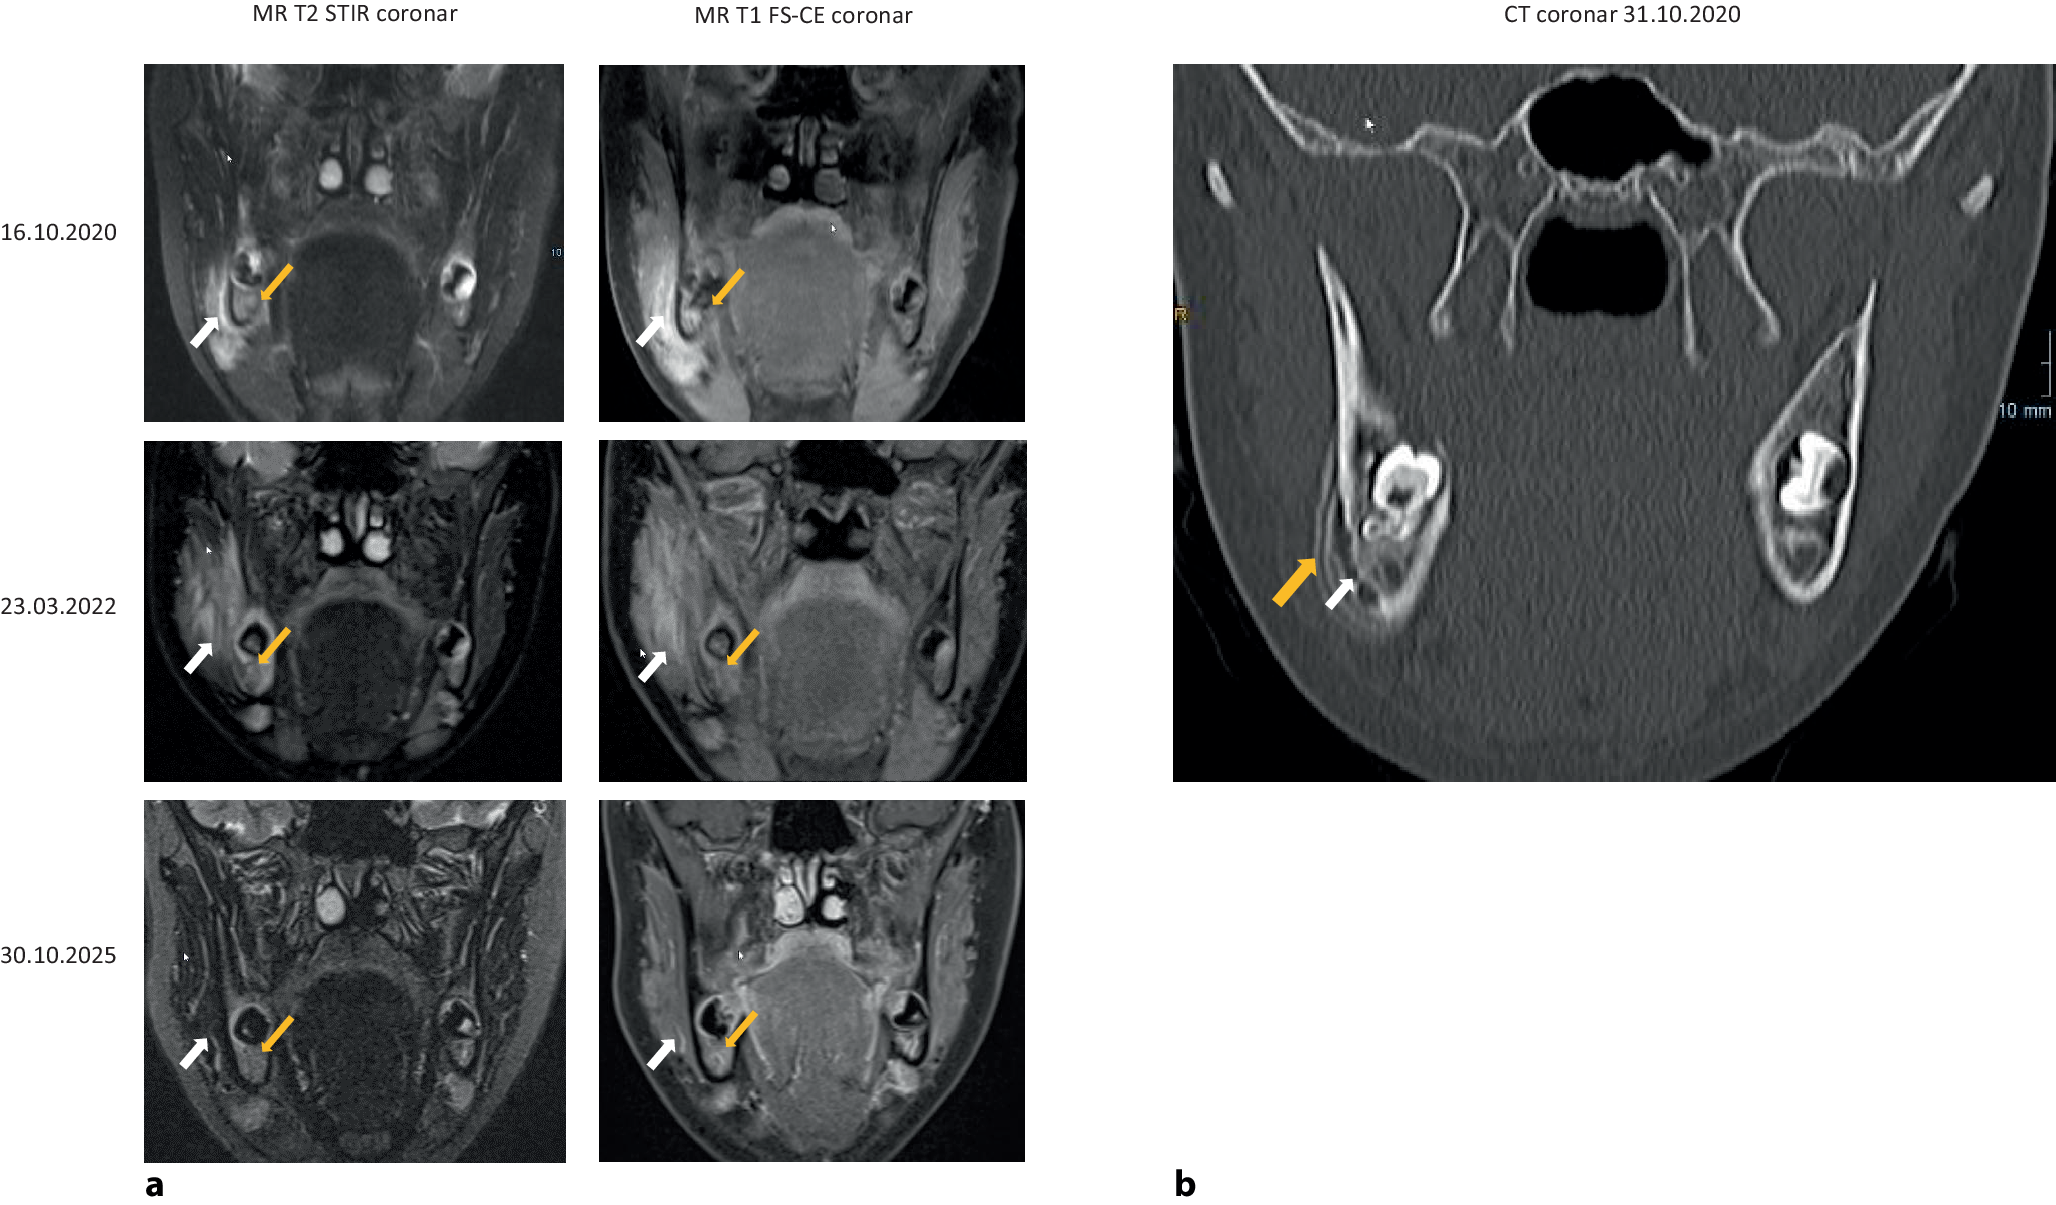

Im Oktober 2020 erfolgte die Vorstellung der damals 13-jährigen Patientin beim Hauszahnarzt zur Abklärung einer Schwellung des rechten Unterkiefers. Es folgten eine 20-tägige Antibiotikatherapie mit Clindamycin sowie eine erste bildgebende Diagnostik mittels MRT (Abb. 1a) und CT (Abb. 1b) sowie eine histologische Untersuchung (externe Mitteilung, s. unten).

Abb. 1

aObere Zeile Die MR-T2-Sequenz koronar mit STIR-Fettunterdrückung (MR T2 STIR cor; linke Spalte) vom 16.10.2020 zeigt ein Knochenödem (Pfeil, gelb) und ein unmittelbar angrenzendes Weichteilödem (Pfeil, weiß). In der MR-T1-Sequenz mit Fettsättigung koronar nach Kontrastmittel (MR T1 FS-CE cor; rechte Spalte) kommen das Knochenödem und das Weichteilödem kontrastreicher und ausgedehnter zur Darstellung (entsprechende Pfeile, gelb bzw. weiß). Mittlere Zeile Die MRT vom 23.03.2022: Die MR-T2-STIR cor zeigt im Vergleich zur Voruntersuchung weiterhin ein deutliches Knochenödem sowie eine flächige Zunahme der Weichteilödemausdehnung. Die MR-T1 FS-CE cor zeigt hier zusätzlich ein stärkeres KM-Enhancement der knöchernen Strukturen und der umgebenden Weichteile. (Pfeilmarkierungen analog obere Zeile). Untere Zeile MRT vom 30.10.2025: MR T2 STIR cor (linke Spalte) und MR T1 FS-CE cor (rechte Spalte): Die knöchernen Strukturen, das Periost und umgebende Weichgewebe zeigen deutlich rückläufige Befunde. Hier finden sich weder in der STIR-Sequenz noch in der KM-Serie signifikant pathologische Signale. (Pfeilmarkierungen, analog obere Zeile). b CT vom 30.10.2020: Die CT zeigt eine Arrosion der Kompakta (weißer Pfeil) sowie eine lamelläre Periostreaktion dort angrenzend (gelber Pfeil)

Die MRT des Gesichtsschädels (Abb. 1a) zeigte ein Ödem der Spongiosa und der benachbarten Weichteile sowie eine ausgedehnte Kontrastmittelreaktion in diesem Areal als Korrelat der CNO im Bereich der Mandibula rechts. Eine Ganzkörper-MRT blieb ohne Nachweis weiterer Knochenödeme oder Gelenkergüsse.

Auch eine vorläufig letzte MRT-Kontrolle am 30.10.2025 (Abb. 1a) zeigte eine Remission der anhaltend beschwerdefreien, inzwischen erwachsenen Patientin, die vor Monaten eine Ausbildung zur Verwaltungsangestellten aufgenommen hat.